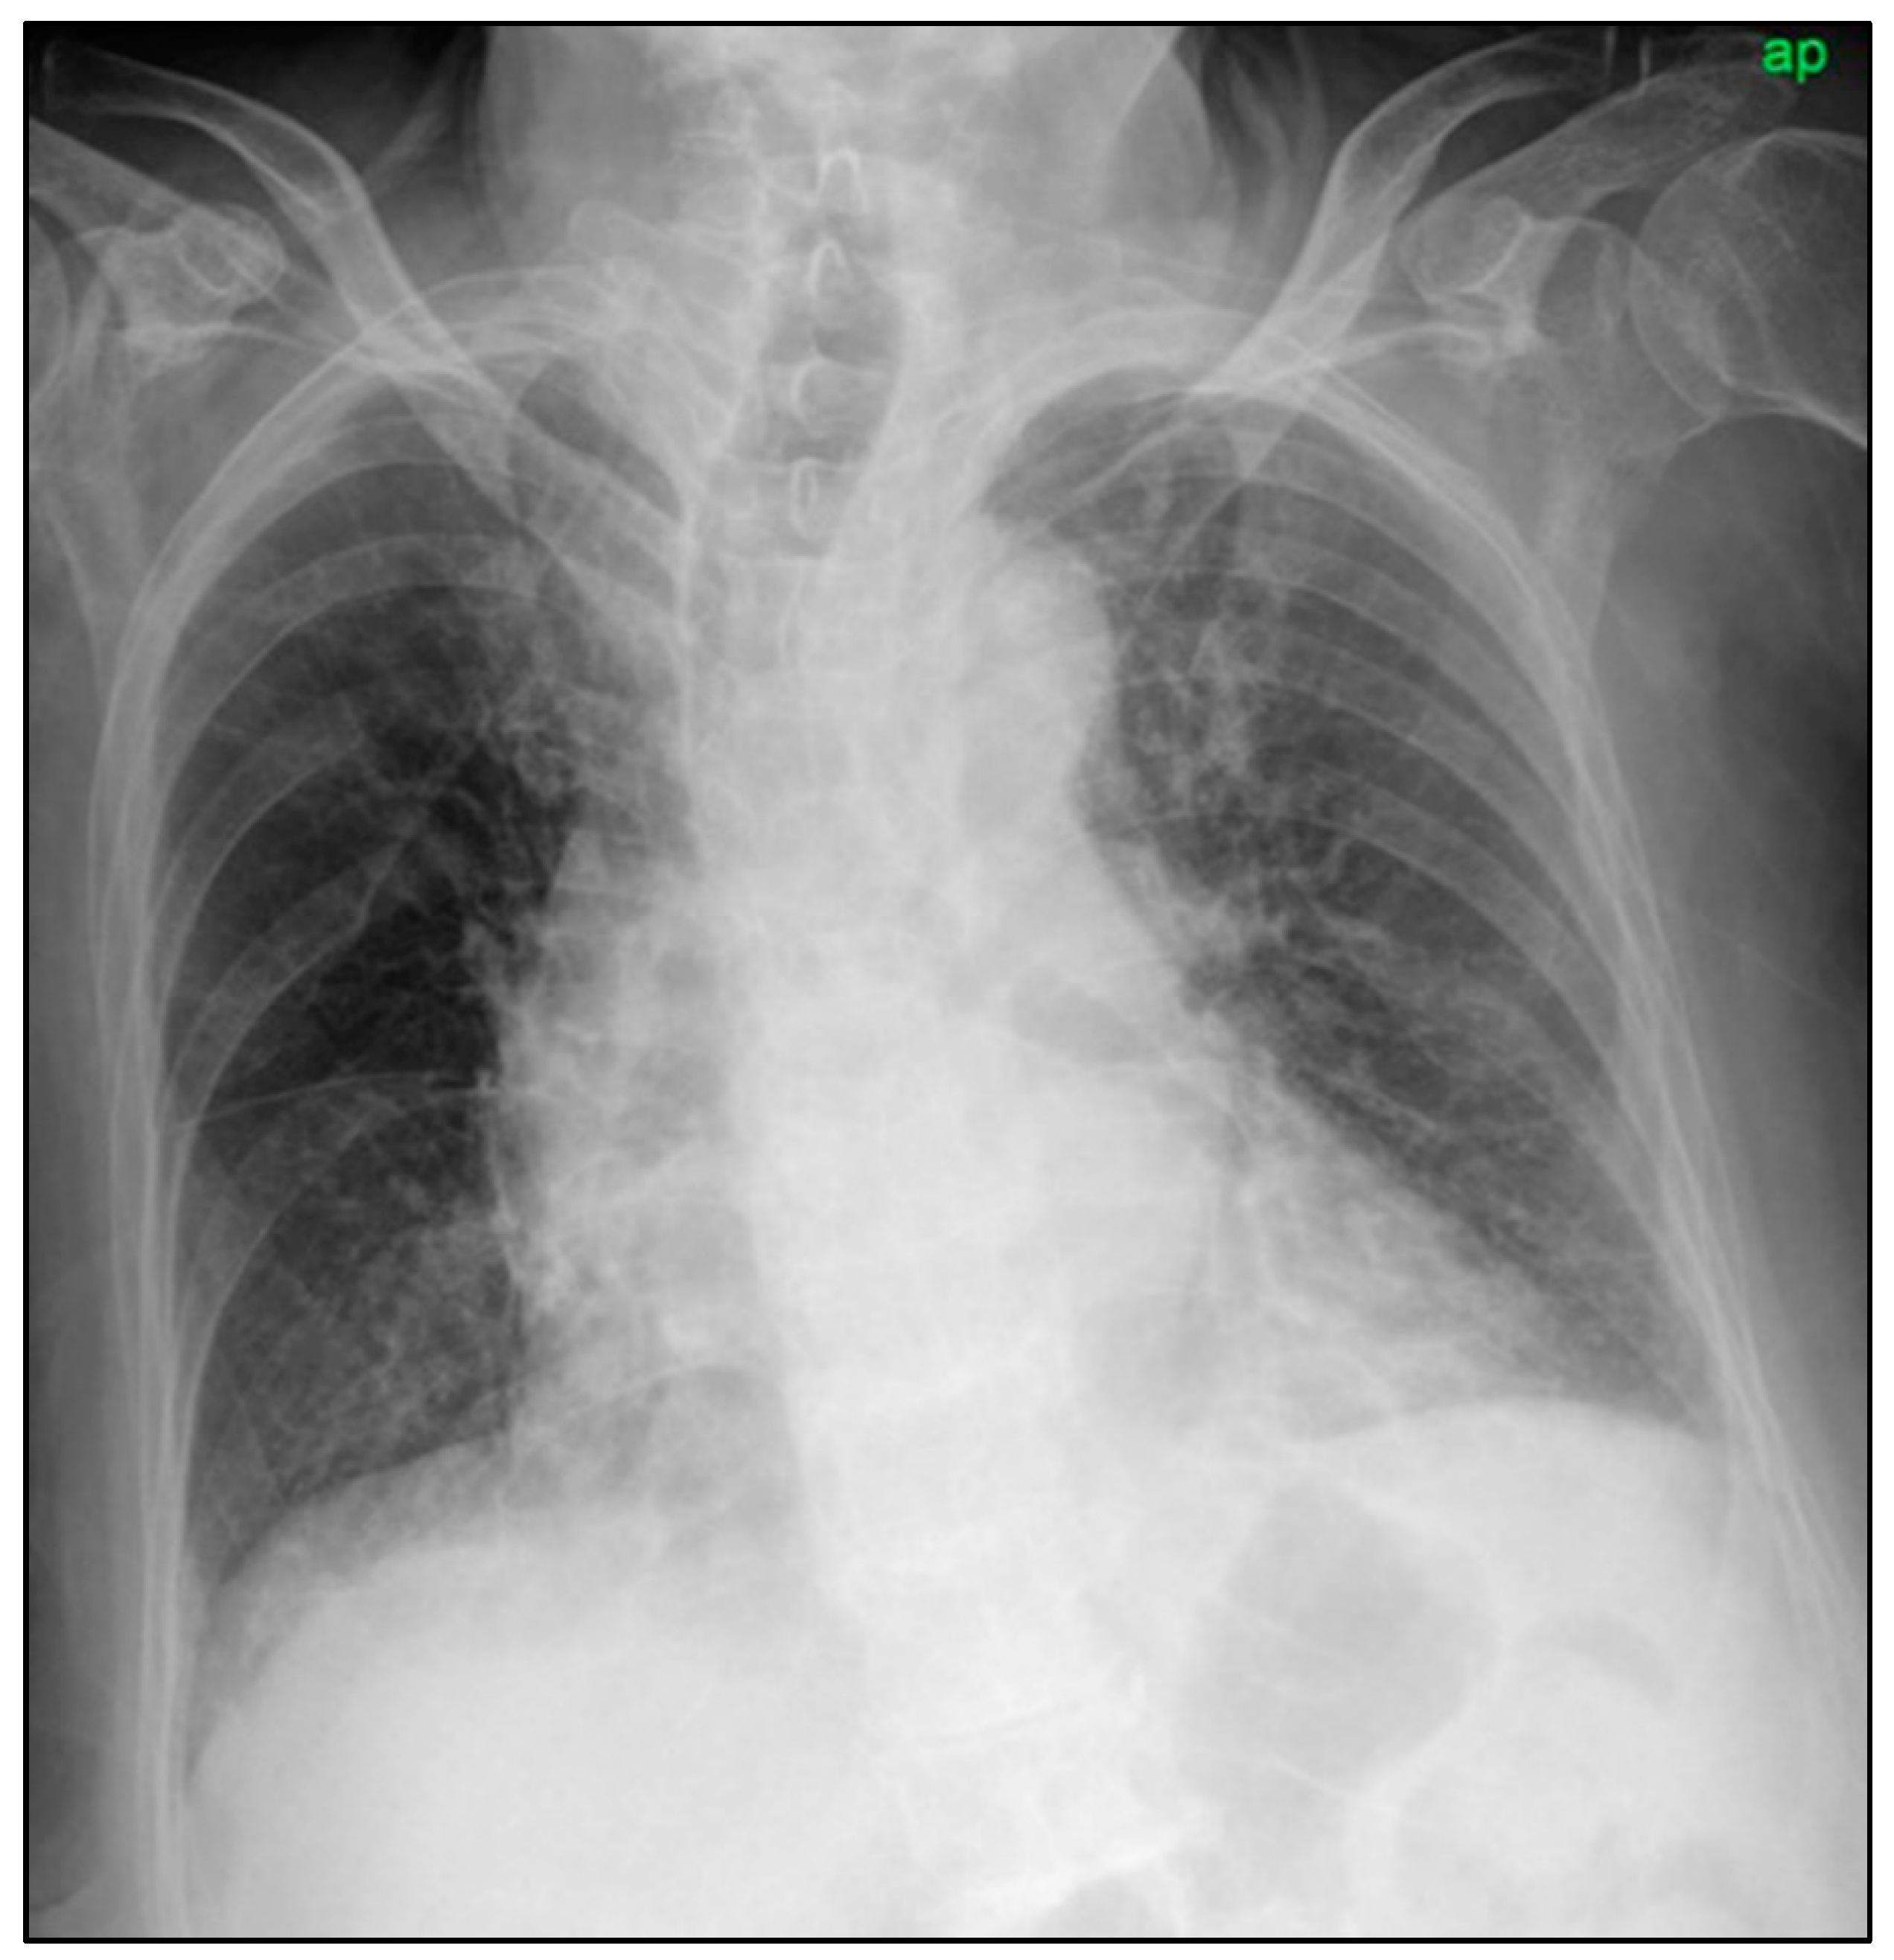

2. Case Report